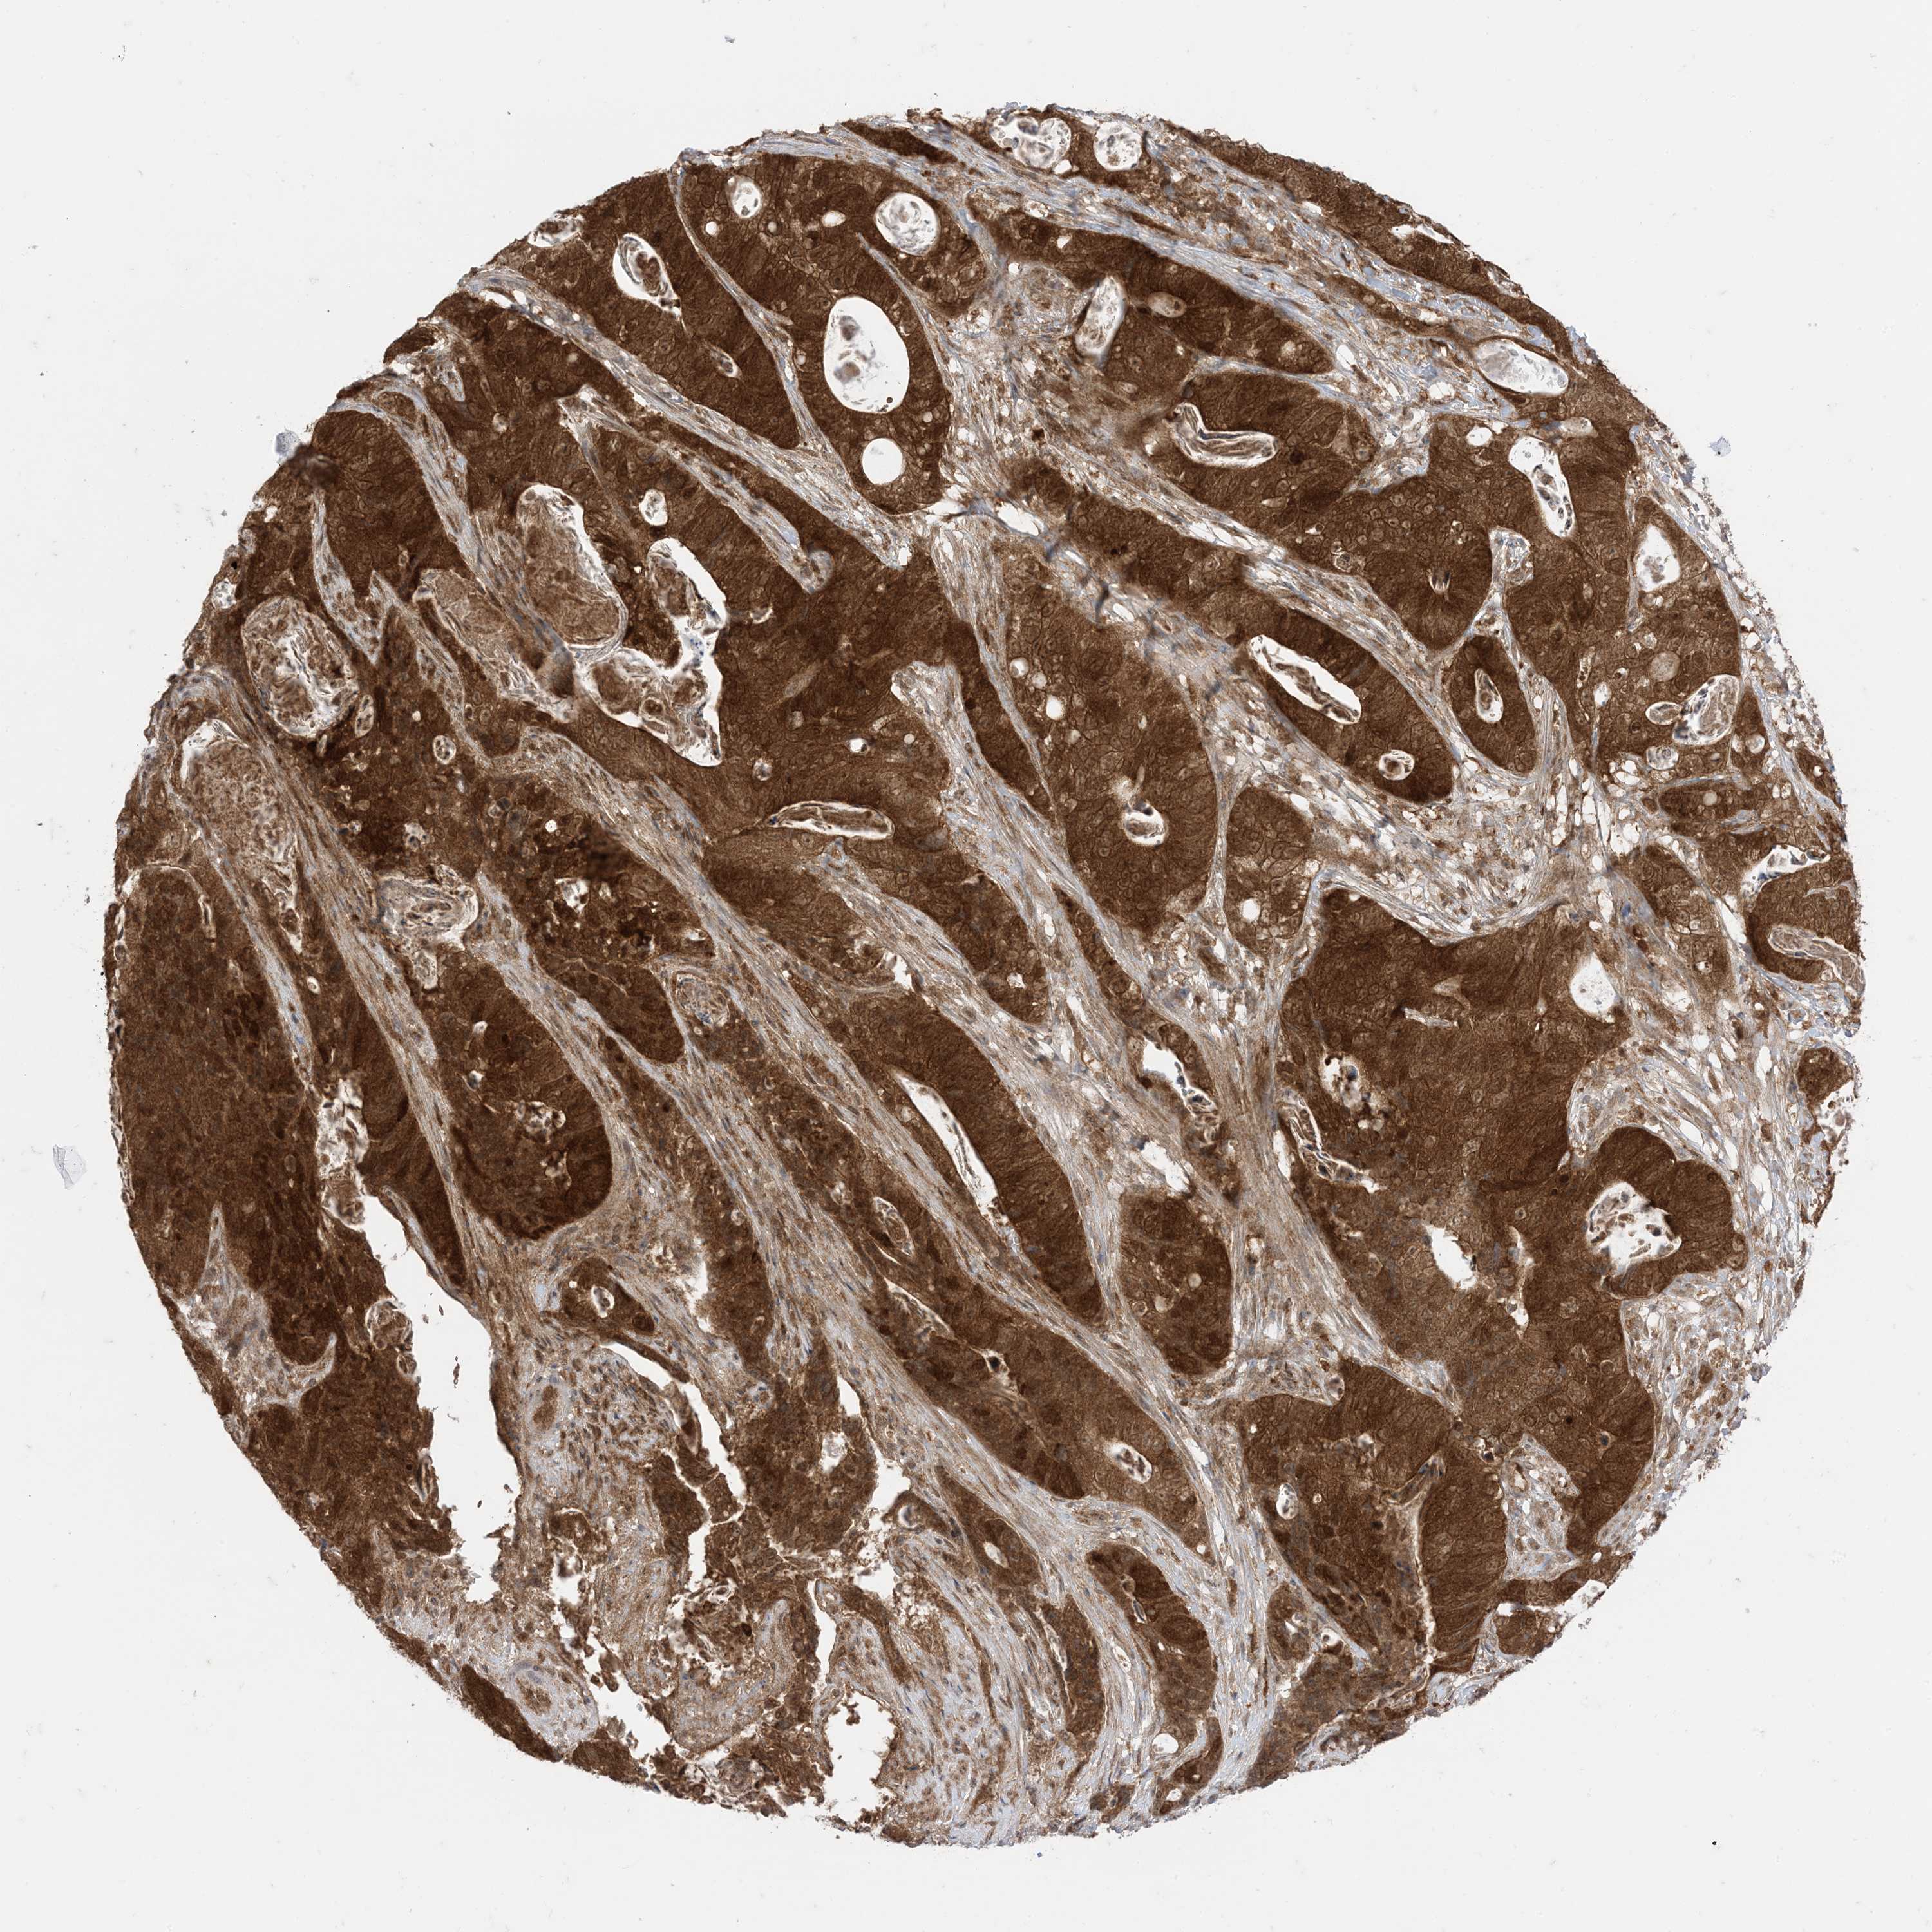

STOMACH CANCER - Protein expressioni

A mouse-over function shows sample information and annotation data. Click on an image to view it in a full screen mode. Samples can be filtered based on level of antibody staining by selecting one or several of the following categories: high, medium, low and not detected. The assay and annotation is described here.

Note that samples used for immunohistochemistry by the Human Protein Atlas do not correspond to samples in the TCGA dataset.

Antibody stainingi

Antibody staining in the annotated cell types in the current human tissue is reported as not detected, low, medium, or high, based on conventional immunohistochemistry profiling in selected tissues. This score is based on the combination of the staining intensity and fraction of stained cells.

Each image is clickable and will lead to virtual microscopy that enables deeper exploration of all samples and also displays staining intensity scores, fraction scores and subcellular localization as well as patient and tissue information for each sample.

HPA005695

CAB022068

CAB035999

CAB080052

CAB080054

CAB080098

Staining

High

Medium

Low

Not detected

Intensity

Strong

Moderate

Weak

Negative

Quantity

>75%

75%-25%

<25%

None

Location

Nuclear

Cytoplasmic/membranous

Cytoplasmic/membranous,nuclear

Adenocarcinoma, NOS

Adenocarcinoma, High grade